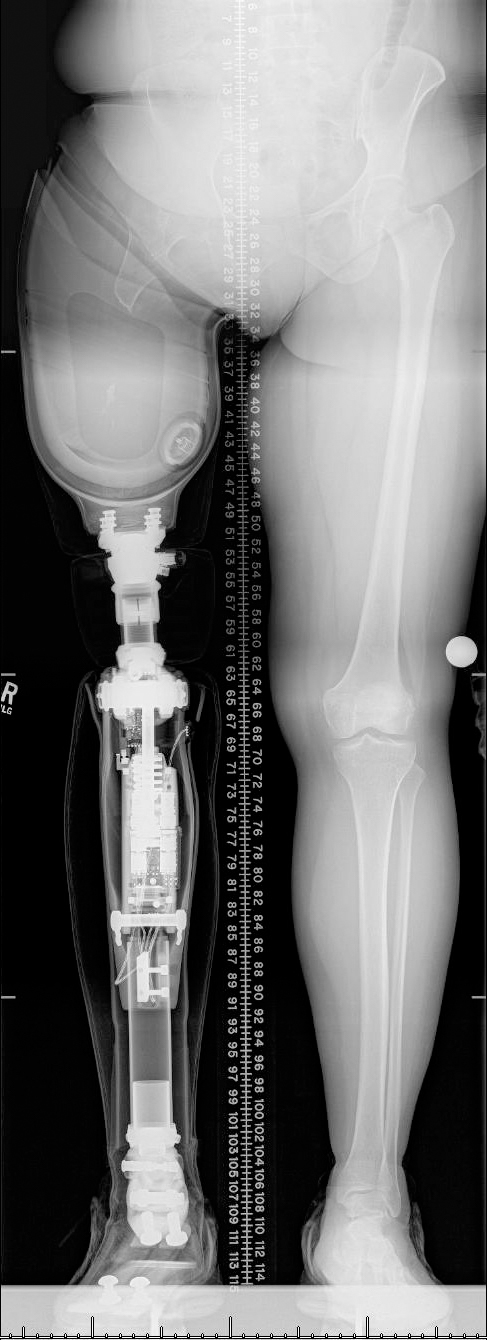

Osseointegration surgery is done in 1 or 2 stages depending on the implant type, design, and individual patient needs. First, a titanium implant is placed into the bone of the residual limb. The implant then extends through the skin and allows for a direct connection to a prosthesis. While healing, the arm or leg implant becomes unified with the bone, which allows the prosthetic limb to act more like a direct extension of the residual limb.

There are two types of osseointegration techniques: screw-fit (OPRA) and press-fit. Press-fit implants are typically done in a single-stage technique and can be performed on multiple locations of the body. Screw-fit (OPRA) implants are only available for transfemoral amputations and are done in a two-stage technique. The Limb Restoration Program offers both types of implants, depending on which technique is most appropriate for the patient’s needs and insurance coverages.